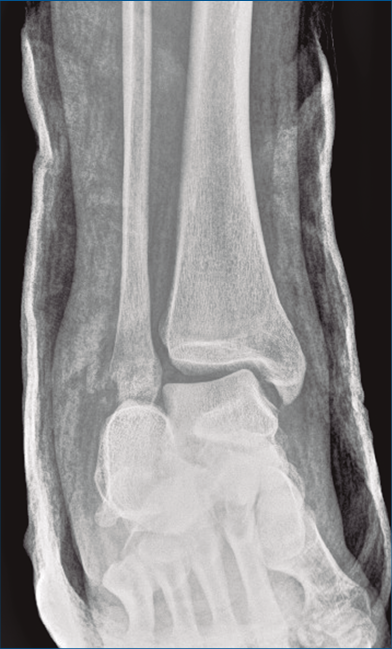

Figura 8. Radiografía anteroposterior de tobillo, inclinación lateral del astrágalo, ocupación del espacio subperoneo, fractura maléolo peroneo y apertura de sindesmosis.

Clínicamente, el primer indicio que nos debe hacer pensar en una fractura luxación de calcáneo, junto con la presencia de dolor, tumefacción y deformidad del retropié, debe ser la luxación anterior de los tendones peroneos(4). Como primera exploración complementaria utilizaremos la radiografía simple. Además del perfil de pie y de la axial de calcáneo, debemos realizar una radiografía dorsoplantar del pie para valorar la articulación calcaneocuboidea y un estudio del tobillo para descartar fracturas del maléolo peroneo, así como para evidenciar la subluxación del astrágalo o lesiones de la sindesmosis. La inversión del astrágalo en la mortaja tibioperonea es una lesión patognomónica de la fractura luxación de calcáneo(2).

Según la literatura, el primer indicio que nos debe hacer pensar en una fractura luxación de calcáneo, junto con la clínica de dolor, tumefacción y deformidad del retropié, debe ser la luxación anterior de los tendones peroneos. Sin embargo, consideramos que en la práctica clínica es muy complejo realizar este diagnóstico específico basándonos únicamente en la exploración física, dada la infrecuencia de las fracturas luxaciones de calcáneo. Por ello, pensamos que la realización de la radiografía anteroposterior de tobillo es básica ante la sospecha clínica de fractura de calcáneo, pues la presencia de una subluxación de astrágalo en la mortaja tibioperonea asociada a una fractura de calcáneo nos debe poner en alerta ante el componente de inversión de esta lesión y la posibilidad de que exista una fractura luxación de calcáneo. La inversión del astrágalo en la mortaja tibioperonea es un signo patognomónico para el diagnóstico de esta compleja lesión. Se evidenciará también con esta proyección la ocupación del espacio submaleolar lateral, normalmente libre.